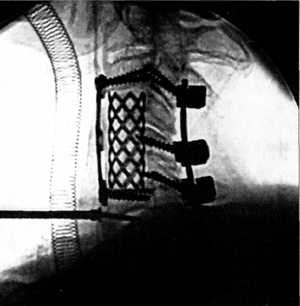

Для заднего спондилодеза в ХНИИОТ использовали, в основном, синтетический шовный

материал, металлическую проволоку, а в последнее время все более широко применяются

разработанные нами оригинальные погружные металлоконструкции. Например, для

достижения максимально точного восстановления анатомических соотношений костных

элементов заднего опорно-связочного комплекса на уровне повреждения в пределах

одного позвоночного двигательного сегмента при разрушении его мягкотканных элементов

и обеспечения надежной фиксации позвонков во вправленном положении нами предложен

фиксатор-стяжка с компенсатором, рац. предложение ХИУВ № 262/96, из проволоки

коррозионностойких сталей марок 12Х18Н9 или 12Х18Н10 диаметром от 1 до 2 мм.

Масса фиксатора невелика, но достаточна для обеспечения стабильной фиксации,

а небольшая длина захватов снижает риск ятрогенного повреждения содержимого

позвоночного канала. Простота изготовления и установки позволяет выполнить стабилизацию

в минимально короткие сроки и снизить травматичность операции. Пластины для